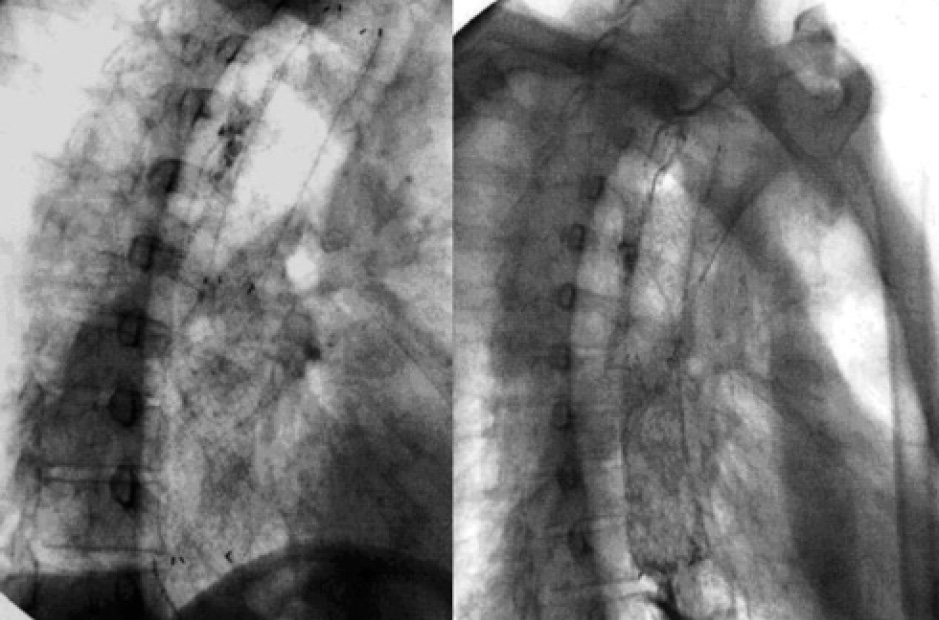

Успешность стентирования пищевода саморасширяющимися стентами составила 100% (технически стенты установлены всем пациентам с первой попытки). Наиболее частой жалобой после проведения стентирования стала загрудинная боль, была отмечена у 62 (77,5%) пациентов. Также мы наблюдали такие грозные осложнения, как перфорация пищевода в результате механического раздвигания стентом тканей опухоли, у 2 (2,5%) пациентов и в 2 (2,5%) случаях наблюдалась миграция стента на 1–2-е сутки. Из поздних осложнений встретились 4 рецидива дисфагии (5,0%) в результате продолженного опухолевого роста над проксимальным участком стента, у 4 (5,0%) пациентов образовался пищеводный свищ (3 трахео-пищеводных свища и 1 пищеводно-плевральный), у 1-го пациента (1,2%) произошло разрушение стента через 2 месяца. В 9 (11,2%) случаях потребовалось рестентирование. Продолжительность жизни после стентирования по поводу злокачественных стриктур составила 6–14 месяцев, медиана 10 месяцев. 2 пациентам проведено стентирование пищевода на фоне постожоговых рубцовых изменений пищевода. Это был первый этап лечения. После нормализации состояния и восстановления пищевого статуса были выполнены пластические операции на пищеводе. В качестве клинического примера приведем интересное наблюдение успешного выполнения стентирования пациенту, перенесшему операцию по поводу рака нижней трети пищевода с наложением эзофагогастроанастамоза. Через полгода после операции у больного возникли жалобы на отхождение мокроты с кровью, дисфагию, кашель, повышение температуры тела. Было проведено обследование, выявлен рецидив рака в зоне желудочного трансплантата с дисфагией III степени. Также в области анастомоза у пациента выявлен бронхо-пищеводный свищ (рис. 2).

Рис. 2. Рентгендиагностика опухоли пищевода и пищеводно-бронхиального свища

Расстояние между свищом и зоной стеноза составило 13 см, что потребовало применения самого длинного стента (максимальная длина в расправленном состоянии 20 см). На контрольном рентгенконтрастном исследовании подтекания в бронхи контраста не отмечено, зона стеноза проходима (рис. 3). Максимальное раскрытие стента происходило не сразу, а в течение нескольких суток. Поэтому динамический рентгенологический контроль является неотъемлемой частью всей методики при установке пищеводных стентов. Рентгенконтрастное исследование выполнялось сразу после окончания стентирования и далее через сутки. Также данное исследование позволяло исключить миграцию стента и перфорацию пищевода.